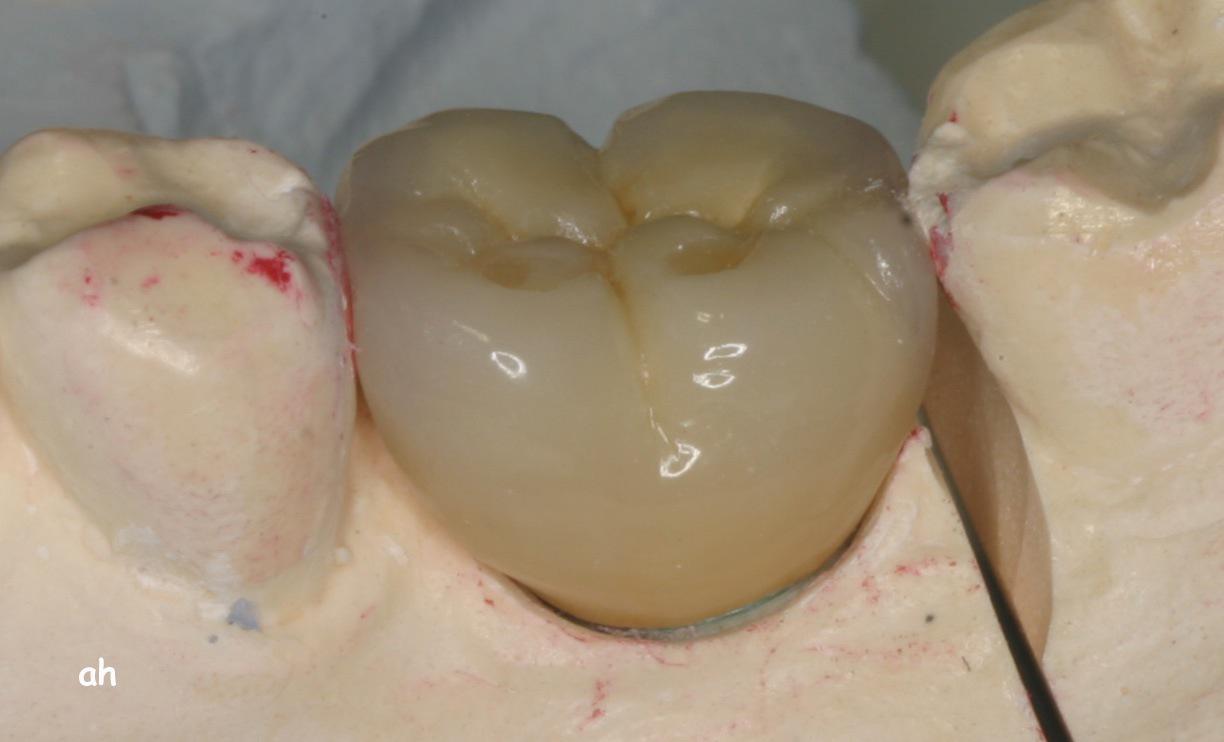

Exemple 2: Un implant remplaçant la racine d'une molaire inférieure gauche.

Exemple 2: La couronne en céramique scellée sur cet implant.